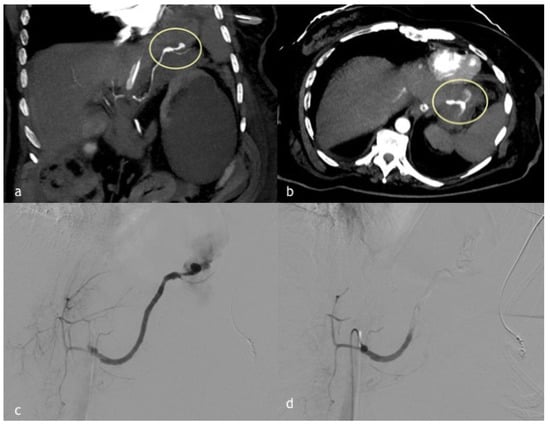

Figure 3. (ad). A 45-year-old woman presented a massive hematemesis after gastroentero-anastomosis due to ingestion of caustics. (a,b) Coronal and axial MPR reconstruction images demonstrate a spastic splenic artery with PSA formation directly bleeding in the stomach (circle). (c) Digital subtraction angiographic image shows splenic artery PSA rupture with massive bleeding in the stomach. (d) Post-embolization angiographic control shows complete occlusion of the splenic artery obtained with 1:1 mixture Glue/Lipiodol.